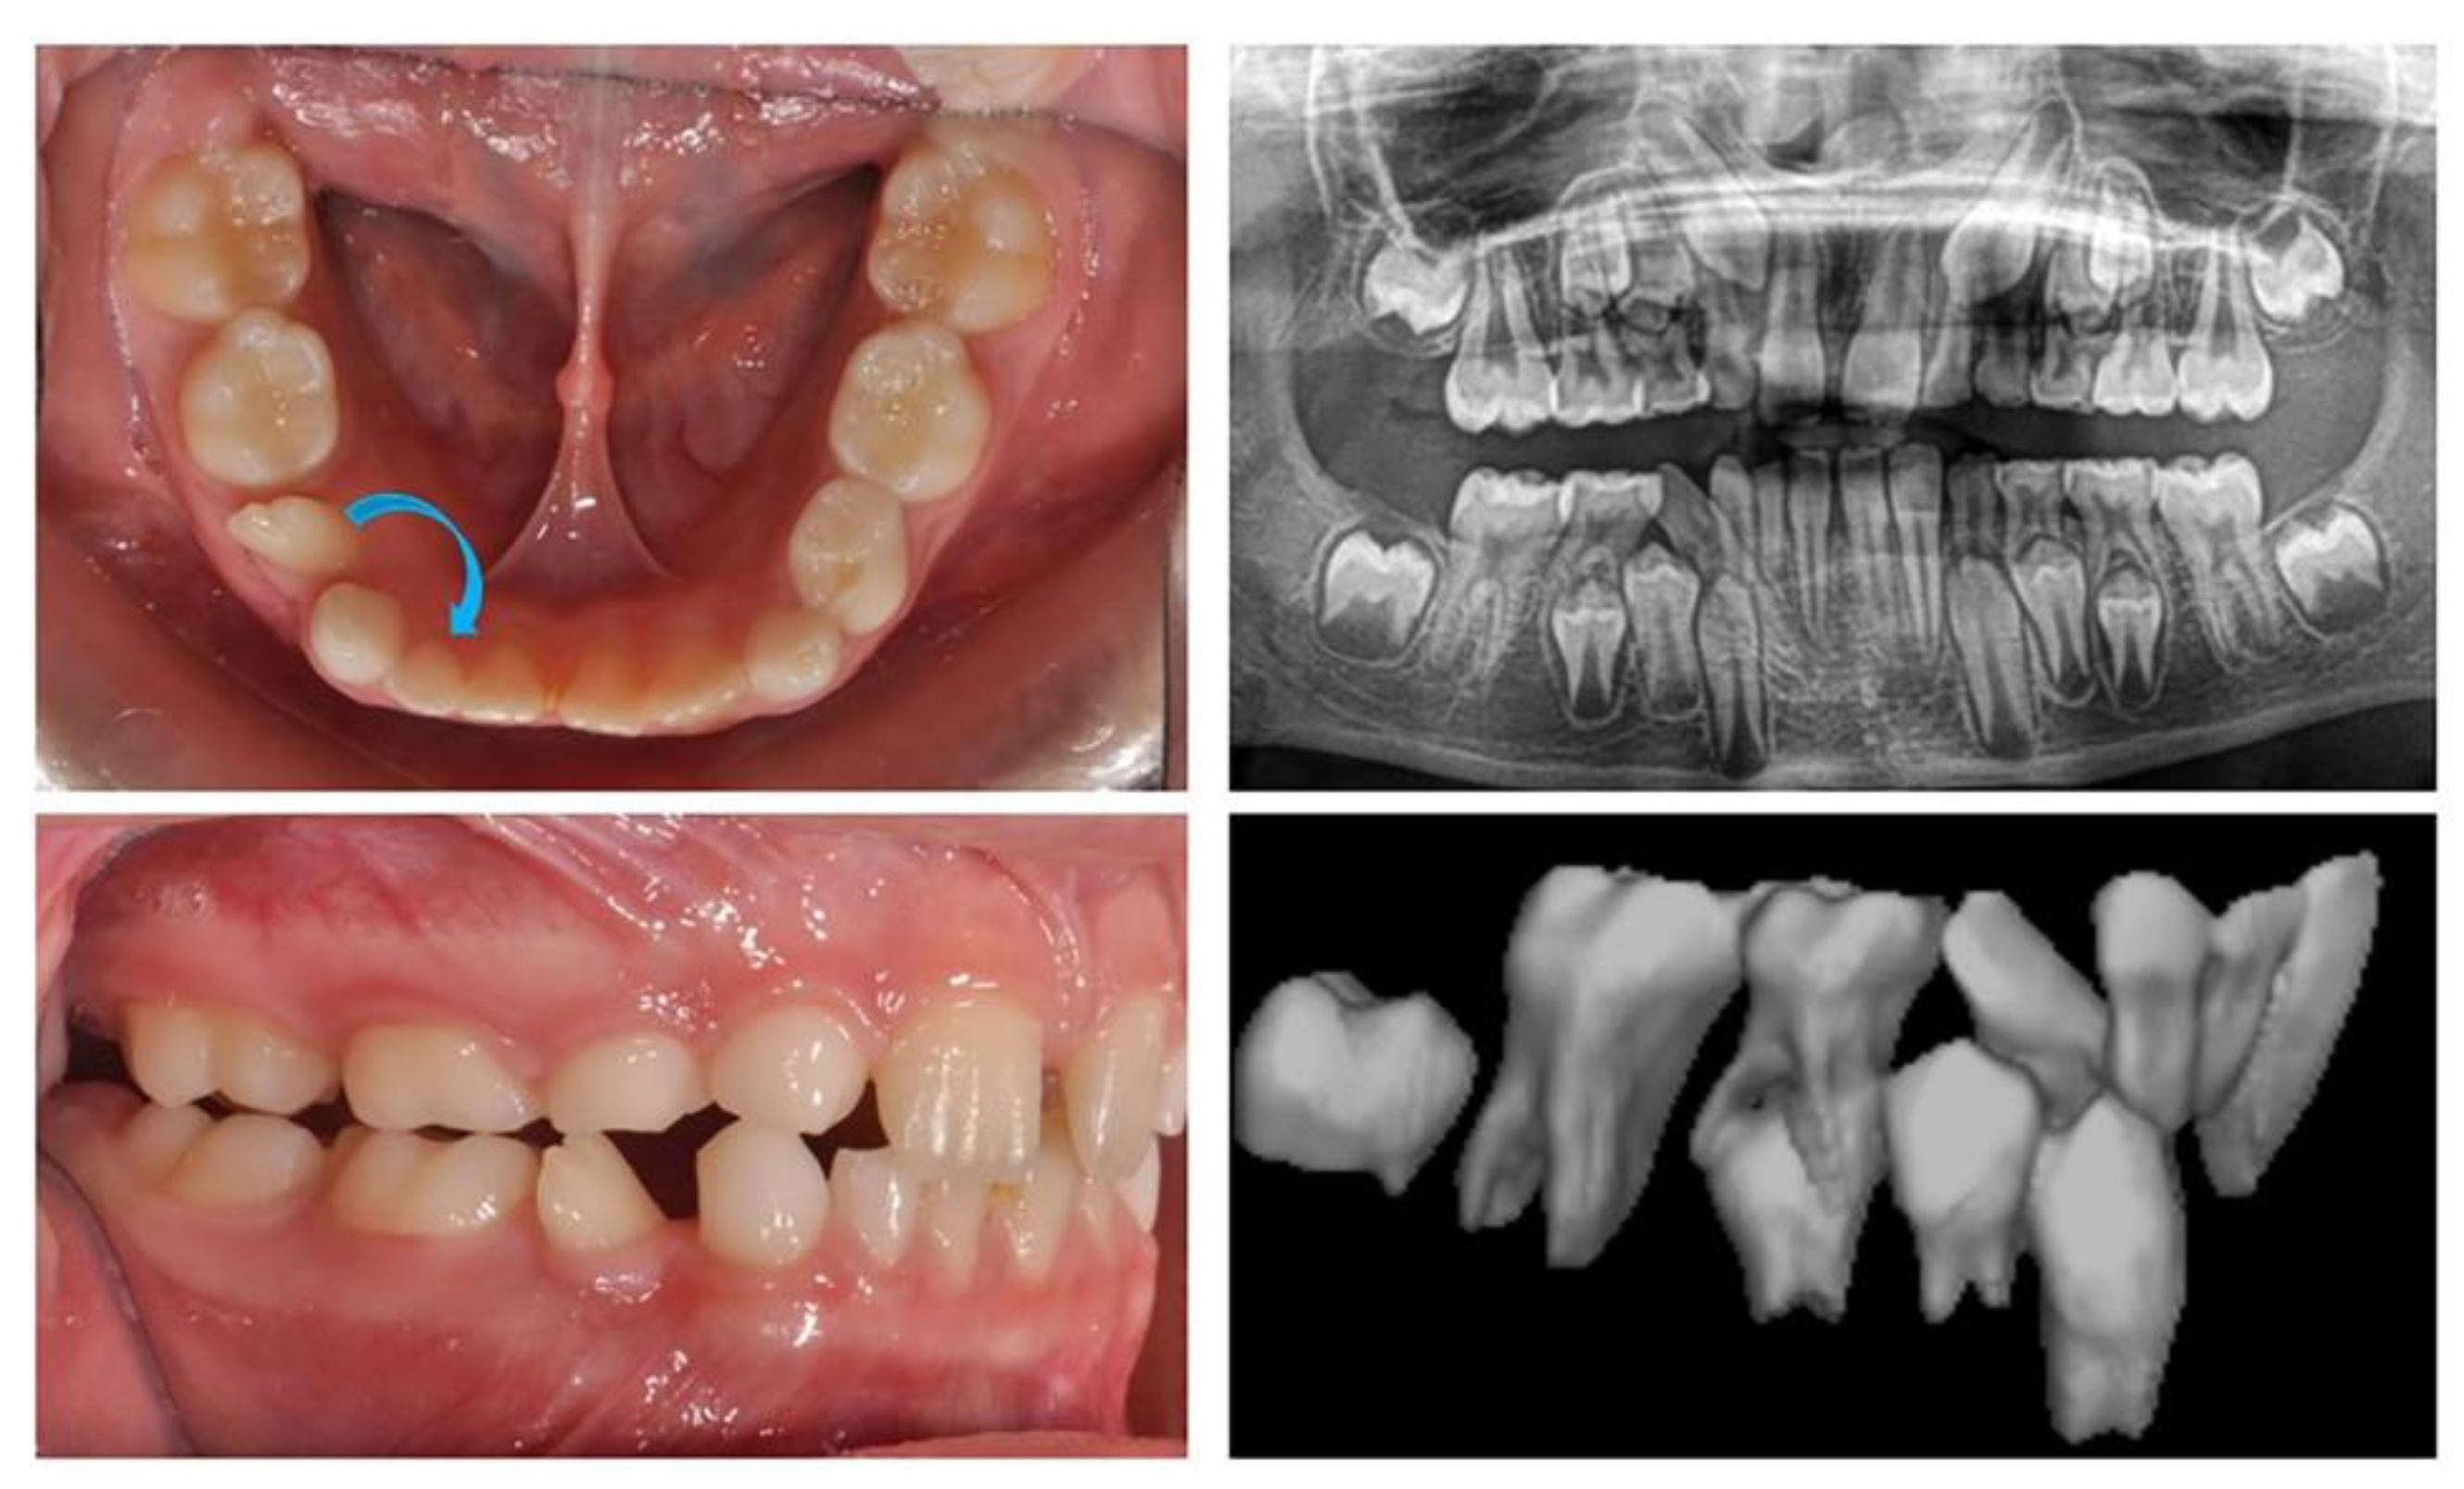

2.2.1 We present an 8-year-old girl with an ectopic eruption of the lower right lateral (42) in the area of the first temporary molar. In the lower dental arch, the temporary right lateral and canine are with preserved positions. After an X-ray examination, hypodontia of the upper laterals was established in the upper dental arch. The well-developed and normally positioned germ of right canines and premolars in the lower were found (Figure 1). In this early phase of mixed dentition, the ectopically placed lower right lateral should be positioned in its normal location. This will prevent future canine transposition or canine retention due to the mechanical barrier that the lateral presents. At the same time, it is important to preserve the perimeter of the dental arch, in the earlier exfoliation of the temporary canine.

Figure 1. Oral clinical status and x-ray examinations of a patient with an ectopic eruption of the lower right lateral (42) in the area of the first temporary molar.